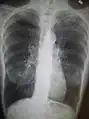

A chest X-ray is not useful to establish a diagnosis of COPD but it is of use in either excluding other conditions or including comorbidities such as pulmonary fibrosis and bronchiectasis. Characteristic signs of COPD on X-ray include hyperinflation (shown by a flattened diaphragm and an increased retrosternal air space) and lung hyperlucency.[5] A saber-sheath trachea may also be shown that is indicative of COPD.[110]

Chest X-ray demonstrating severe COPD, displaying small heart size in comparison to the lungs

Chest X-ray demonstrating severe COPD, displaying small heart size in comparison to the lungs A lateral chest X-ray of a person with emphysema, displaying barrel chest and flat diaphragm